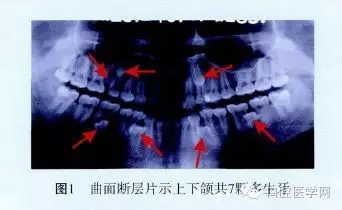

曲面斷層片顯示:15與16之間有2顆多生牙;23根尖1顆多生牙,牙冠與根尖重疊;43與44、33與34兩根尖1/3處各有1顆多生牙;36根尖可見1顆水平向多生牙,牙冠朝向37根近中,根尖與36根尖重疊;46根分叉下方有1顆多生牙;上下頜共有7顆多生牙(圖1)。